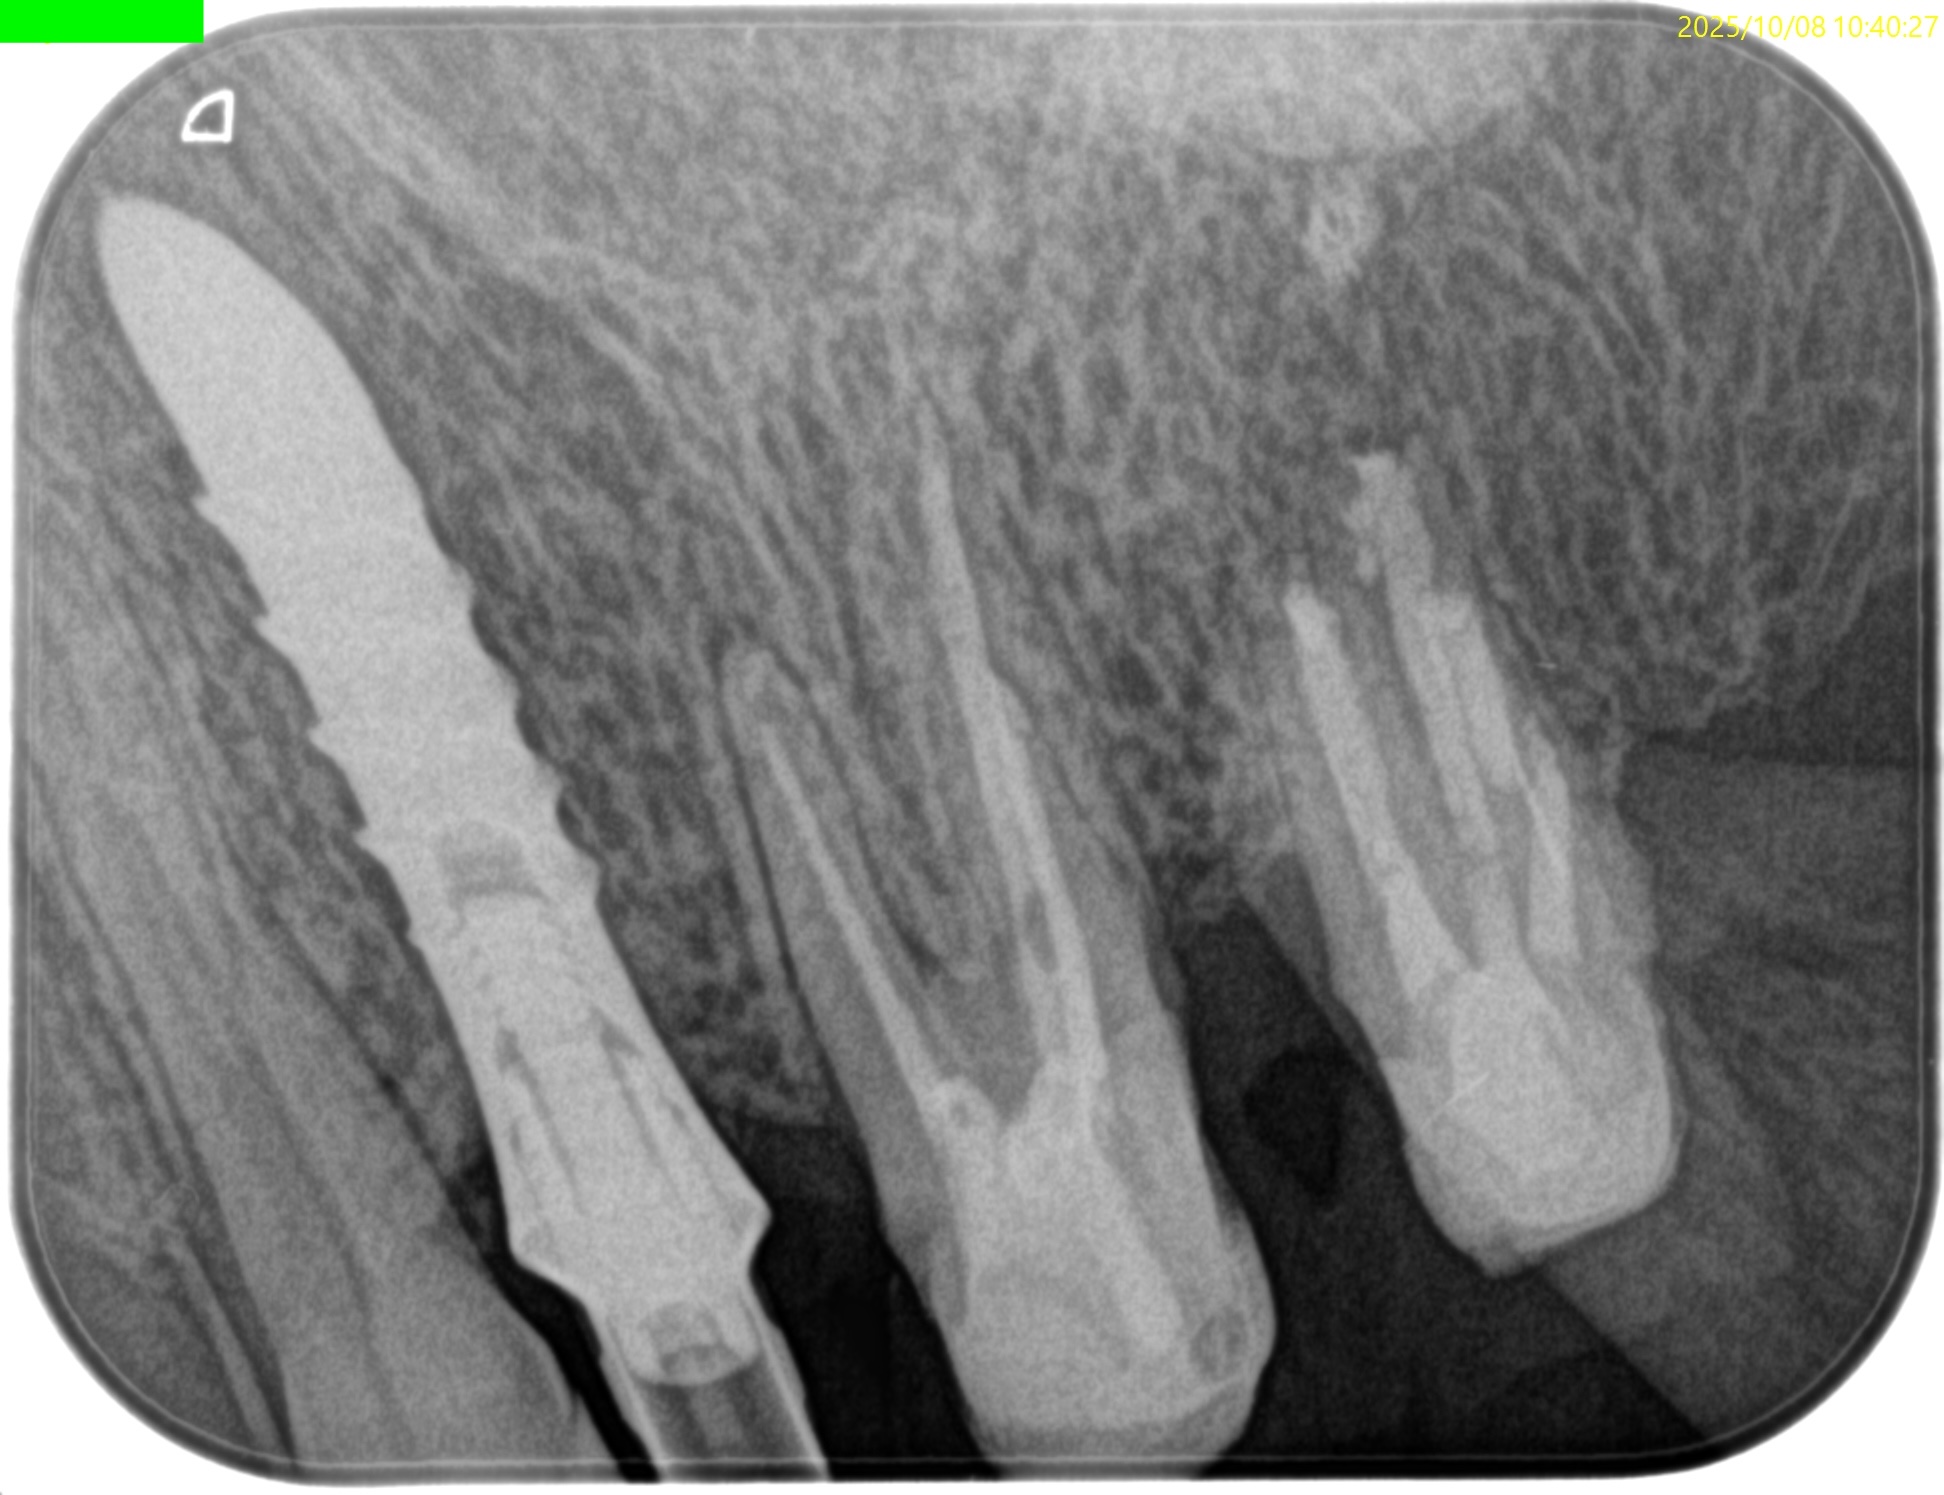

#15 Intentional Replantation 6M recall(2025.10.8)

術直後と比較した。

歯槽骨がだいぶ回復している。

最終補綴もOKだ。